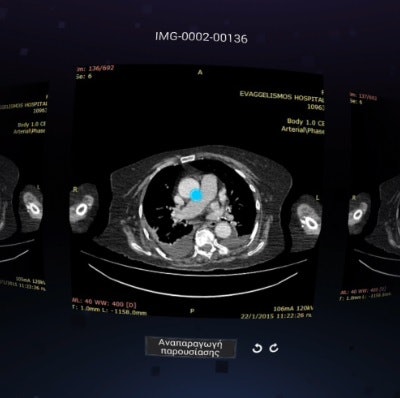

After modifying virtual reality hardware and software to be able to support the viewing of DICOM images, a team from Evangelismos Hospital in Athens found it could produce more than 97% interobserver agreement in testing on 271 CT studies.

The researchers tested the device using 271 complete CT exams from 138 patients; some of the patients had been examined more than once and many had received multiple scans. The patients were scanned for various indications and the exams were reviewed by a consultant radiologist in the hospital. All types of CT scans (abdomen, brain, chest, lungs, and spine) and both with and without contrast were included in the research study.

Next, the CT exams were independently and remotely reviewed in a blinded fashion by another consultant radiologist using the virtual-reality system. Five critical checkpoints (such as the presence of intracranial hemorrhage, width of ventricular system, midline structure alignment, density of white matter, and middle cerebral artery density for brain imaging) were used for each of the 271 examinations, leading to a total of 1,355 total results in the study.